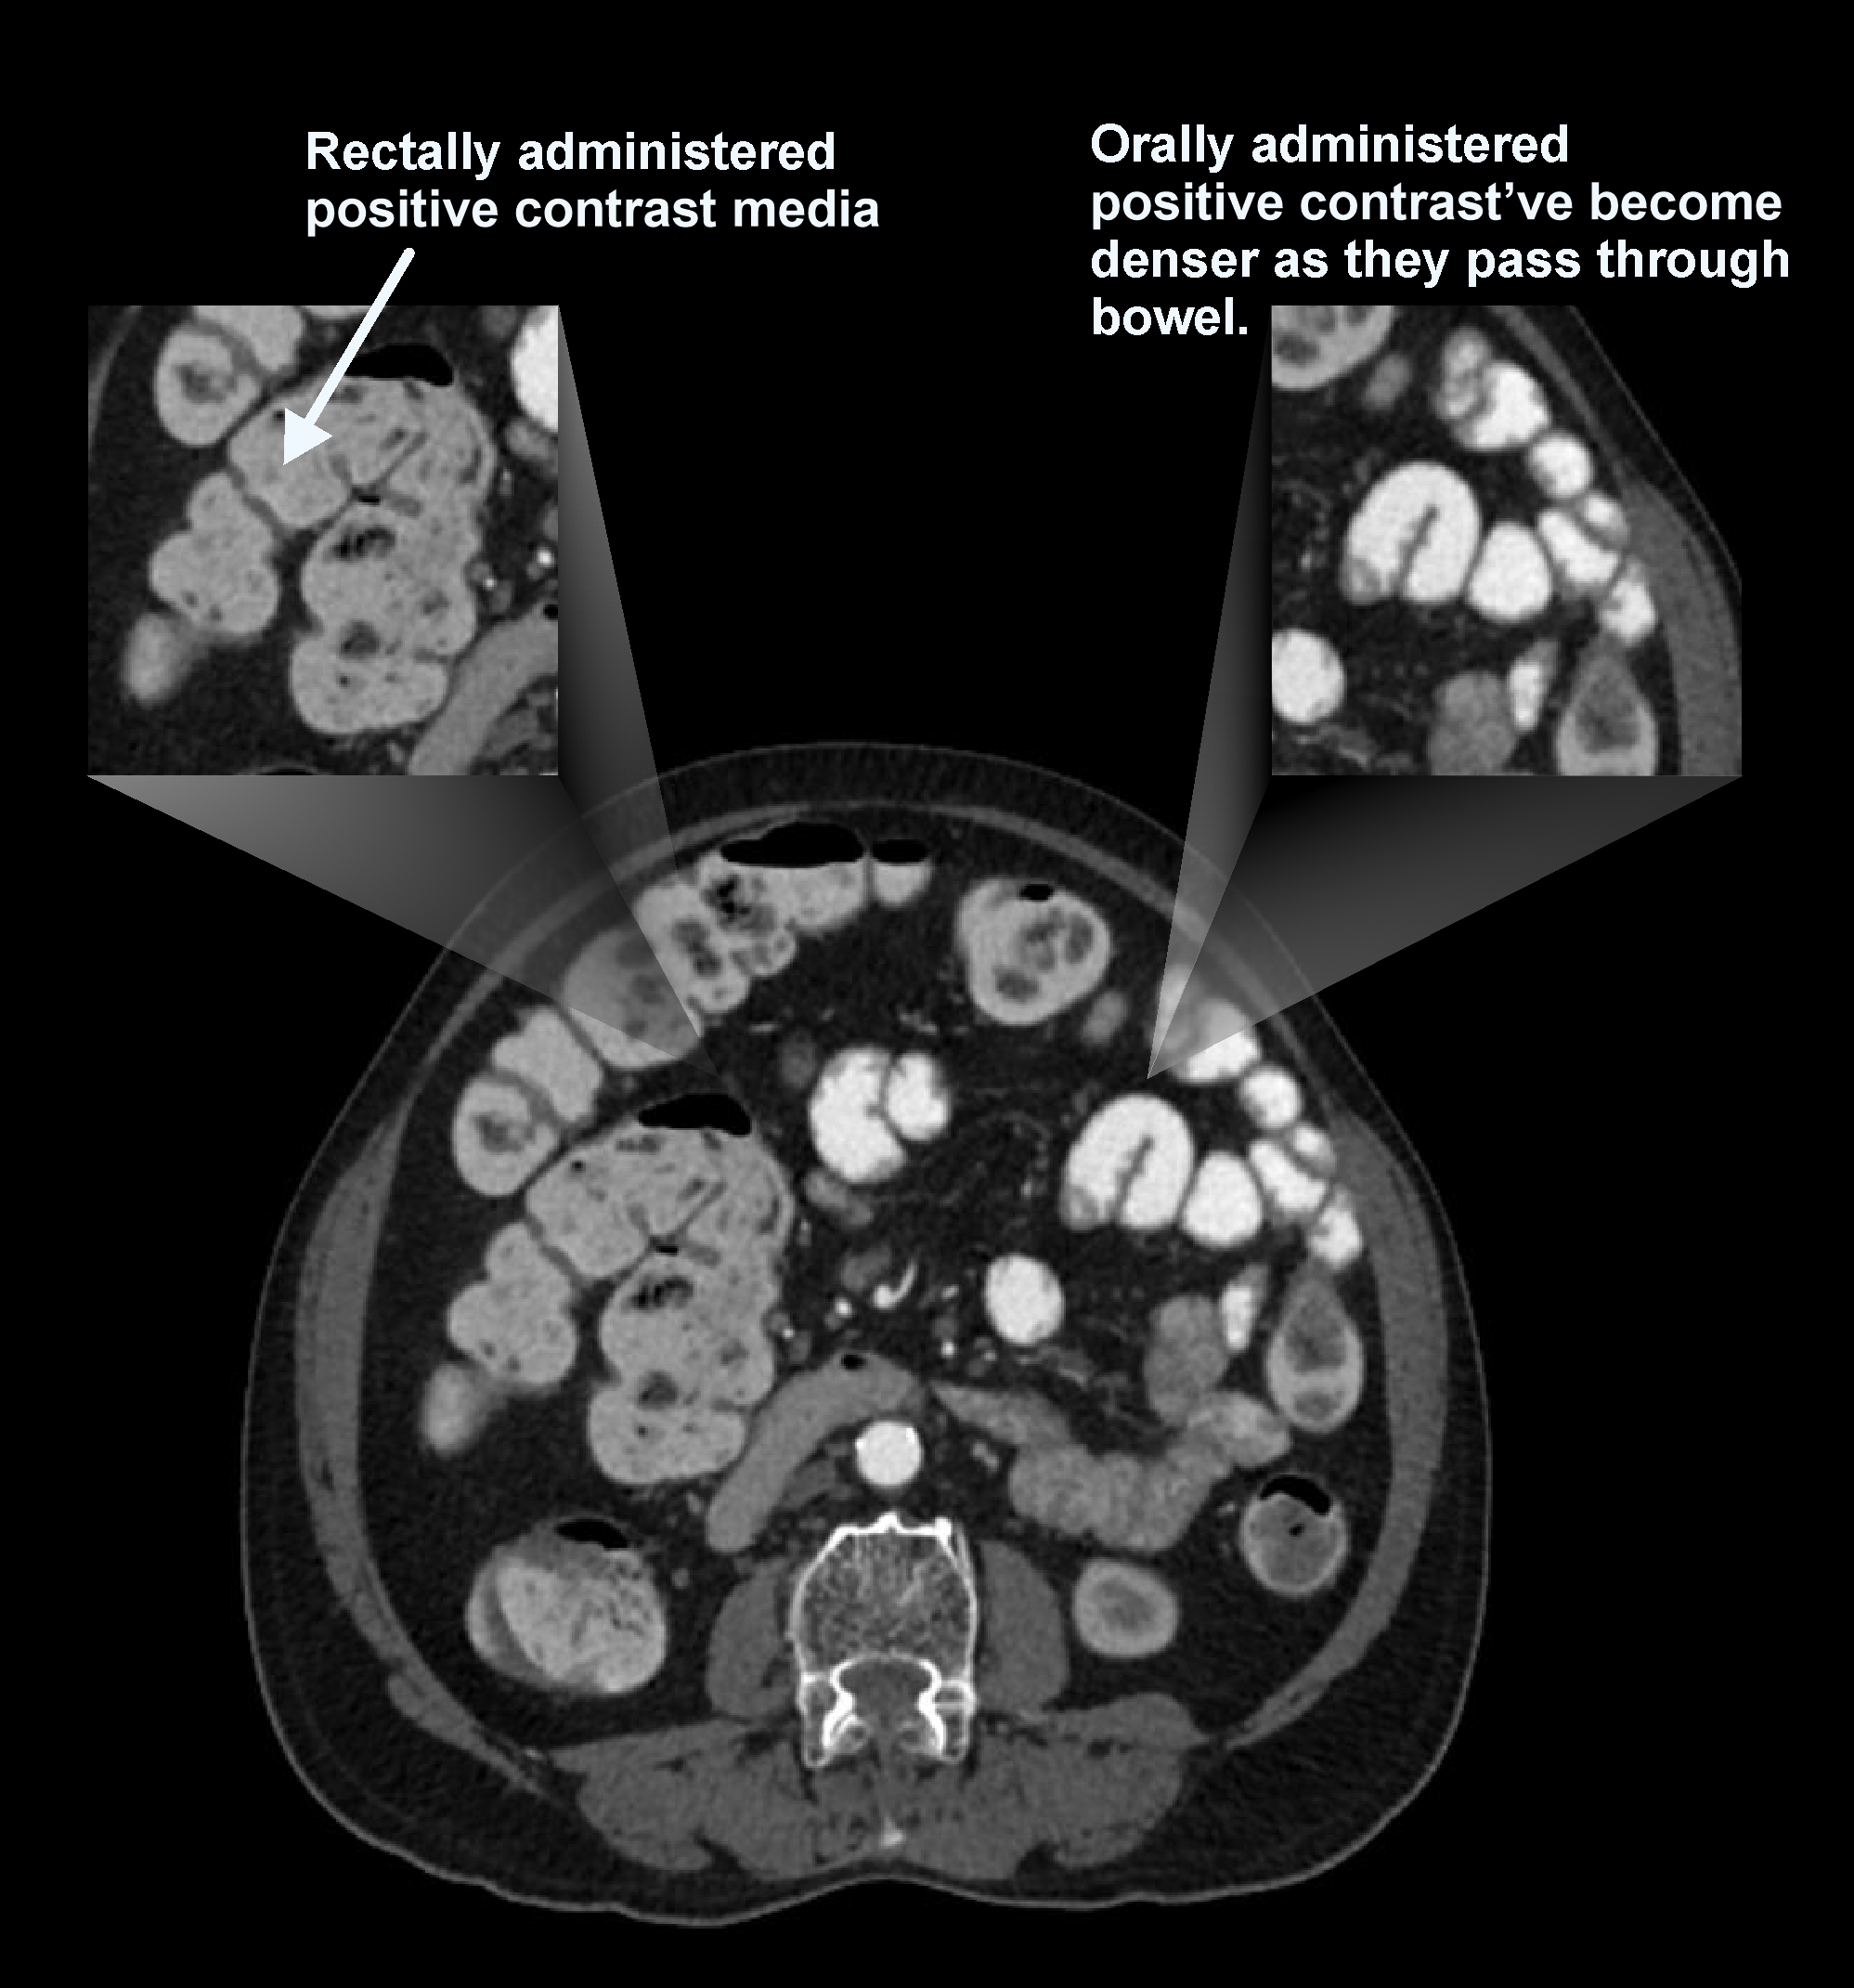

b. Positive contrast media

Contrast media in this category have the highest density (positive HU value), which appear bright on images. Iodinated contrast and barium sulphate are commonly used as positive contrast. Their brighter appearance in bowel lumen help to identify abscess, suspected leaks, peritoneal implants, and intra-abdominal tumors. Nevertheless, positive contrast obscures the visualization of bowel wall enhancement patterns, and can’t be used in angiograms where 3D-reformation is needed.

Explanation: Intraluminal contrast media is mainly used to distend bowel and improve visualization of bowel pathologies. Contrast administration is usually done orally or rectally, or both. Oral administration fills stomach and small bowel. In contrast, rectal administration fills mainly the colon. Mannitol, which has slow absorption rate, can be given orally to fill the entire GI track. In comparison, water is only capable of reaching the proximal part of bowel due to its rapid absorption if administered orally.